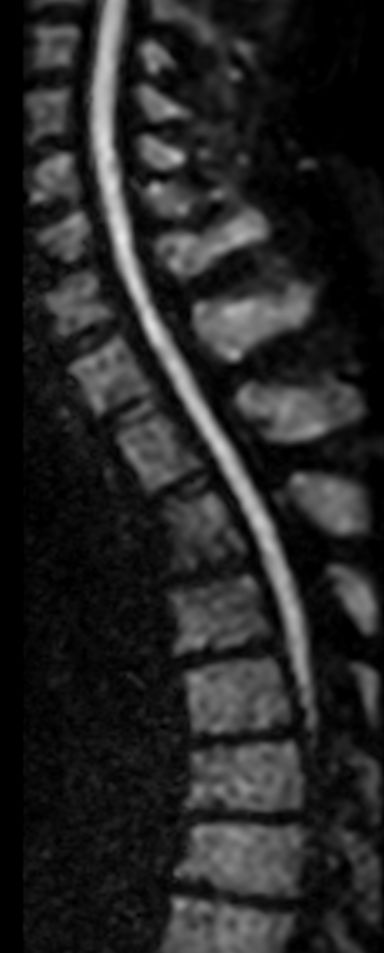

Sagittal Diffusion IRIS Zoom (b800)